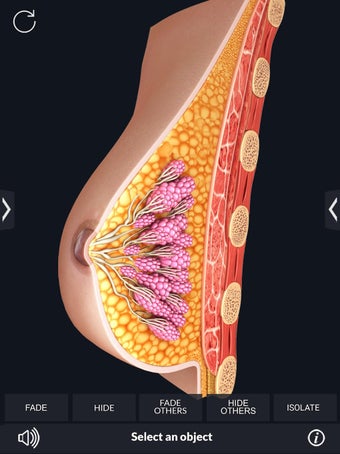

My Organs Anatomy es una aplicación de anatomía 3D gratuita desarrollada por Visual 3D Science para usuarios de Android. Esta aplicación proporciona un modelo 3D altamente realista de los órganos humanos que se puede girar 360°, acercar y alejar, y ver desde cualquier ángulo. La aplicación está diseñada para proporcionar una mirada detallada a la anatomía de los órganos humanos y ofrece varias características para ayudar a los usuarios a explorar y aprender.

La interfaz fácil de usar de My Organs Anatomy permite una navegación sencilla, lo que facilita la selección, rayos X, ocultación y visualización de órganos individuales. La aplicación también incluye un modo de animación, opciones de búsqueda y un panel de información que proporciona información relacionada. Además, la aplicación ofrece pronunciación de audio para todos los términos anatómicos, e incluso los usuarios pueden dibujar o escribir en la pantalla y compartir capturas de pantalla.